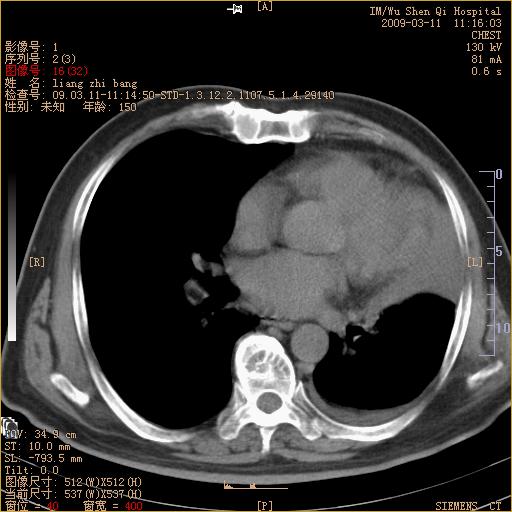

标题: CT18604:男,60岁,咳嗽一月余 [打印本页]

标题: CT18604:男,60岁,咳嗽一月余

1)考虑左肺上叶中央型肺癌并左肺上叶肺不张;建议必要时行纤支镜检查进一步明确诊断。2)左侧胸腔积液。

考虑左肺上叶中央型肺癌并左肺上叶肺不张

肺门肿块、支气管开口闭塞伴肺不张及胸水!典型的中心型肺癌变现!

1、左肺上叶中央型肺癌并上叶阻塞性肺不张。

2、左侧胸腔少量积液,右侧胸膜轻度增厚。

左肺们肿块并左肺上叶不张。考虑左肺中心性肺癌并左肺上叶不张及左侧胸腔积液